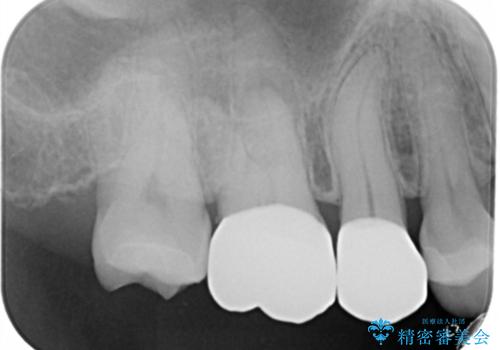

- 右上7番の銀歯のやりかえを主訴に来院された患者様です。

切削量・形態を考慮し、セラミックインレーでの治療を計画しました。

インレー治療では自分の歯を多く残すことが出来ます。